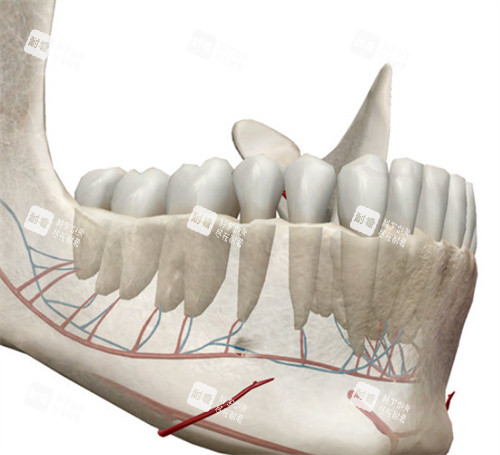

万启龙的“正畸-正颌联合治疗”,核心就俩字:“配合”。术前正畸先通过牙套调整牙齿位置,把“歪七扭八”的牙排整齐,消除牙齿的“代偿性倾斜”(比如地包天患者为了咬合,下牙会故意往前长);术中正颌再精细切割、移动颌骨,把“错位的骨头”摆回正位;术后正畸然后“微调”,让牙齿和骨头理想贴合,咬合稳如“齿轮”。

颌面手术是“在骨头上绣花”,稍有不慎就可能伤到神经、血管,导致面瘫、牙齿松动。万启龙用“计算机辅助设计+3D打印导板”,术前模拟手术过程,术中用导板定位,把骨头移动的误差控制在0.5毫米内,确保术后咬合稳、面部对称。